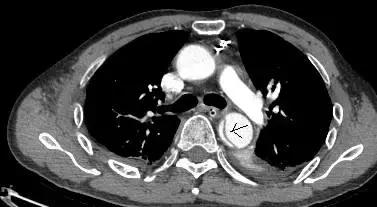

病例七

平扫CT提示升主动脉及降主动脉内膜片,CTA证实为A型主动脉壁间血肿。